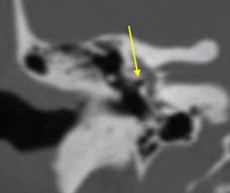

Tomografia

La evaluación mediante tomografía es fundamental para identificar los focos otoscleróticos, principalmente en la ventana oval a nivel de la fissula antefenestran, la cual es un surco que se localiza entre la ventana oval y el proceso cocleariforme. En la fase otospongiótica o activa de la otosclerosis, se pueden observar áreas hipodensas en el hueso, mientras que en la fase inactiva otosclerótica, se observara hueso compacto que puede afectar progresivamente la platina del estribo, provocando la fijación de este.

El grosor normal de la ventana oval se establece en 1.64 mm; valores superiores a 3 mm son considerados compatibles con otosclerosis. En un bajo porcentaje, alrededor del 10%, se presenta un subtipo retrofenestral, que afecta la cápsula ótica y puede resultar en desmineralización, lo que se clasifica como "otosclerosis muy avanzada", según lo definido por House y Sheehy.93 A continuación, se detallan las diferentes clasificaciones relacionadas con esta patología (Tabla 2 y 3).

Tamaño del nicho de la ventana oval: Valores de 1,4 mm se toma como límite inferior de la normalidad. Valores menores se asociaban con un riesgo mayor de tener dificultades técnicas durante la cirugía del estribo. Debe descartarse una otosclerosis obliterativa (Fig. 4-5). |

Figura 4. Vista de la ventana oval en un corte coronal del oído medio |

Figura 5. Ventana oval obliterativa de oído derecho en un corte coronal de oído medio |